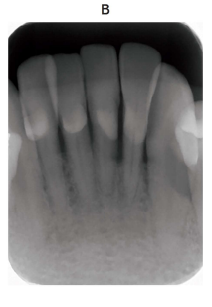

118回 A-32

下顎左側第一大臼歯の口腔内写真(別冊No. 8A)とエックス線画像(別冊No. 8B)を別に示す。

治療方針で適切なのはどれか。 2 つ選べ。

解答:b c

解説:

X線画像より、根分岐部にプローブが完全に通りそうである。⇒3度の根分岐病変

a GTR 法:2度

b 歯根分離:3度

c トンネリング:3度

d FGF-2 製剤の応用:2度

e ファーケーションプラスティ:1,2度